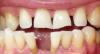

Античелюсть Опубликовано 5 августа, 2011 Поделиться Опубликовано 5 августа, 2011 (изменено) Уважаемые профессионалы, прошу совета. 35 лет полного пофигизма по отношению к собственным зубам за плечами. Щербинка с рождения, но после 16-ти разъехалась до безобразия. Есть и другие проблемы с зубами но пока надо решить проблему с фасадом.Несмотря на то, что было несколько вариантов исправления, вплоть до брекетов, чтобы сдвинуть зубы обратно, пару лет назад сгоряча по совету врача депульпировал четыре передних зуба для постановки моста, то есть с вариантом определился, вернее врач за меня определил после депульпирования отвлекся и зубами не занимался, сейчас продолжил, но несмотря на то, что медицина за это время шагнула вперед даже в такой глухомани, как славный город Волгоград, врач по прежнему советует мост и металлокерамику. Почитав форум - я в сомнении, стоит ли ставить м\керамику, так как доступен оксид циркония и алюминия (клиник, которые используют е-макс не нашел, походив по сайтам местных клиник).Основной довод врача следующий: "зубы у Вас безобразные, мертвые, зачем тратиться на оксид циркония? поберегите свои деньги, поэтому мост и м\кераммика - для Вас предел мечтаний, бла-бла-бла". Действительно ли все так плохо и цельнокерамическая конструкия будет пустой тратой денег? В общем то м\керамика смущает страшилками которые вычитал здесь - синии десны, какие то щели с забившейся пищей, запахи и пр. А может черт на самом деле не так страшен? Тогда сэкономлю и в самом деле. PS может туда посередине имплант воткнуть вобще? PS фото прикладываю, на фото, где "вид ниж челюсти сверху" видно, что десна ушла и передние зубы сильно оголены, от этого или нет, они как будто бы субъективно по ощущениям подвижны, и это беспокоит, можно ли на них мост вообще цеплять. Буду благодарен за любую помощь, очень нужен совет компетентного специалиста, пок родилась мысль походить по разным клиникам поконсультироваться из нескольких мнений выудить лучший вариант избавления от щербинки. Изменено 5 августа, 2011 пользователем Античелюсть Ссылка на комментарий

Алехандро Опубликовано 7 августа, 2011 Поделиться Опубликовано 7 августа, 2011 (изменено) Вам необходимо комплексное восстановление зубов. Замещение диастемы между нижними резцами будет временным решением, как например заплатка на дороге. Имплантат я бы туда не устанавливал. Вот очень примерный план, который можно прикинуть по фашим фото. 1) Диагностика - осмотр нескольких специалистов (ортодонт, ортопед, терапевт, имплантолог) - фотографирование - компьютерная томография, телерентгенограмма - изготовление диагностических моделей ваших зубных рядов 2) Лечение - эндодонтическая ревизия и санация (перелечивание корневых каналов некоторых зубов и устранение кариозных дефектов) - удаление зуба/зубов, которые не рационально оставлять - ортодонтическое лечение (испраление прикуса) - костная пластика и имплантация ( делаются параллельно испралению прикуса) - протезирование (восстановление отсутствующих или разрушенных зубов) Изменено 7 августа, 2011 пользователем Алехандро Ссылка на комментарий

Алехандро Опубликовано 7 августа, 2011 Поделиться Опубликовано 7 августа, 2011 Это будет эпопея не на один месяц, видимо, а что же с эстетикой - продолжать ходить щербатым или съемный зубик пока поносить? (честно говоря не представляю как это на практике). Я Вам предложил план капитального ремонта. Если у Вас нет времени или финансовой возможности, то можно всё провернуть растянув схему лечения. На этапе диагностики нужно решить закрывать Вам щербинку(с) ортопедически или ортодонтически и от этого будет зависеть Ваша эстетическая реабилитация. Если будет принято решение смещать зубы и таким образом уйдёт щель, то конечно нельзя сейчас ставить туда искуственный зуб. Если принимается решение о закрытии щербинки(с) ортопедическим путём, то на период лечения можно сделать временную конструкцию. Тот вариант комплексной реабилитации, которую я Вам накидал, может занять 1.5 - 2 года. Можно всё сделать "дёшево и сердито" - не исправляя прикуса наделать мостов. Это займёт несколько месяцев. Экспресс вариант имеет множество недостатков, но по такой схеме у нас в стране работают большинство стоматологов. Это называется по старинке. Вы сейчас должны для себя выбрать два пути: лечиться или вылечиться. Ссылка на комментарий